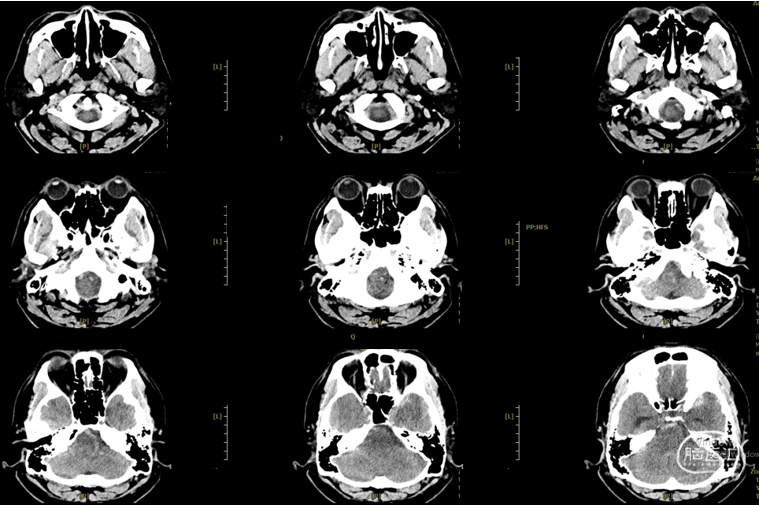

辅助检查:头胸部CT平扫2026-03-14我院脑出血并破入脑室,请结合临床复查,蛛网膜下腔出血。双肺少许纤维灶,双肺坠积性改变,请结合临床隔期复查,双肺少许小结节,考虑低危结节可能,建议结合临床年度随诊复查双肺部分小叶间隔增厚,肺水肿不除外,建议结合临床短期复查,冠脉壁钙化灶,胆囊结石。头颈部CTA2026-03-14我院颅内动脉轻度粥样硬化性改变,左侧优势型椎动脉,椎基底动脉迂曲延长。

初步诊断:1. 左侧额、岛叶、基底节脑出血破入脑室动静脉畸形?2. 脑疝;3. 高血压病3级(极高危)?4. 肺炎;5. 肺结节;6. 胆囊结石;7. 肺水肿;8. 脑动脉粥样硬化。